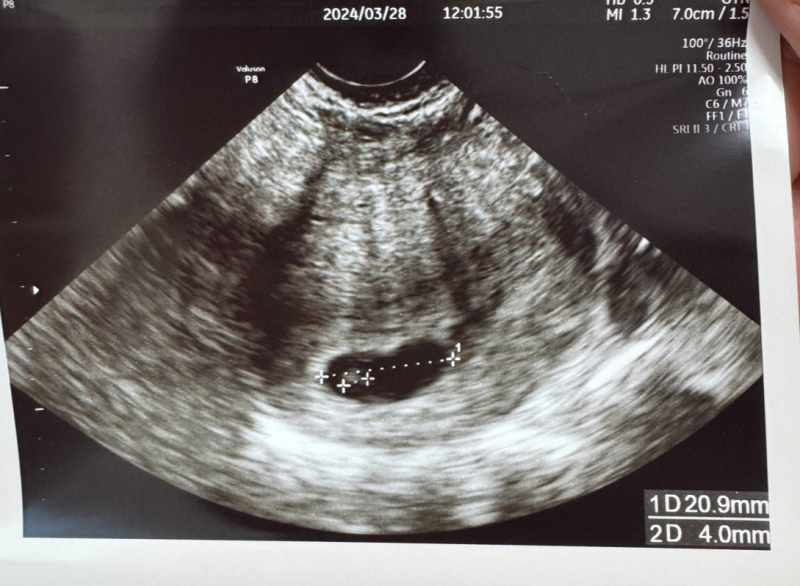

7w1d 胎嚢20.9mm 胎芽4mm 心拍あり

と3/28 7w1dの検診の日には言われています。

エコーは7w1dのものです。